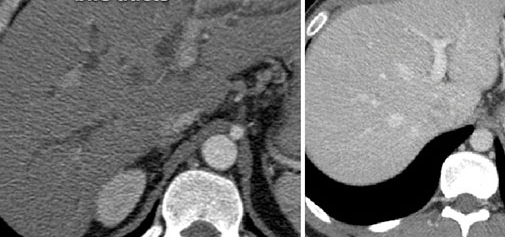

Очаг некроза в легком: снимок без контраста слева и с контрастом справа

Снимок легкого до введения контраста (слева) и после (справа — выявлены патологические очаги)